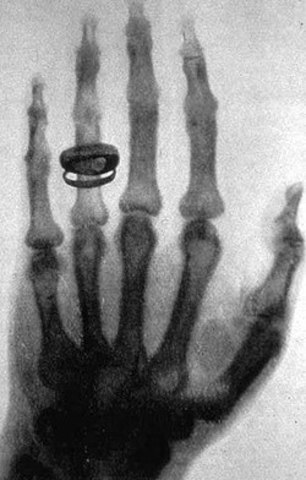

• Descubrimiento de los Rayos X

Descubrimiento de los Rayos X

por el físico alemán Wilhelm Rontgen : el 8 de noviembre de 1895 Röntgen produjo radiación electromagnética en las longitudes de onda correspondiente a los actualmente llamados rayos X